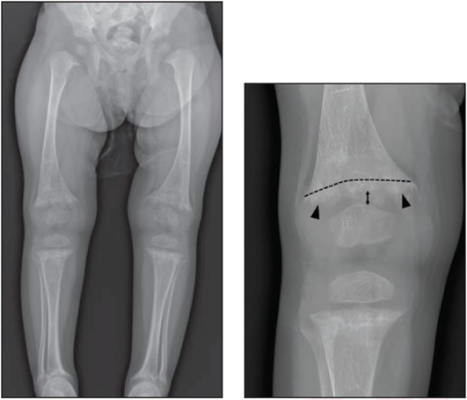

21-месячная девочка с рахитом и уровнем витамина D 5 нг/мл. Слева: двусторонняя рентгенограмма длинных нижних конечностей. Справа: отредактированная рентгенограмма правого колена показывает чашеобразную форму (изогнутая пунктирная линия), истирание (стрелки) и увеличенное расширение физического тела (двойная стрелка) в дистальном отделе бедренной кости с аналогичными данными в проксимальном отделе большеберцовой кости и малоберцовой кости (не аннотировано), все соответствует рахиту. ; на рентгенограмме признаков ХМЛ нет. Все восемь рентгенологов правильно интерпретировали рентгенограмму как показывающую рахит с умеренной или высокой достоверностью.

Согласно Американскому журналу рентгенологии ( AJR) ARRS, рахит и классические метафизарные поражения (ХМЛ) имеют различные рентгенологические признаки, и рентгенологи могут надежно дифференцировать эти два состояния.